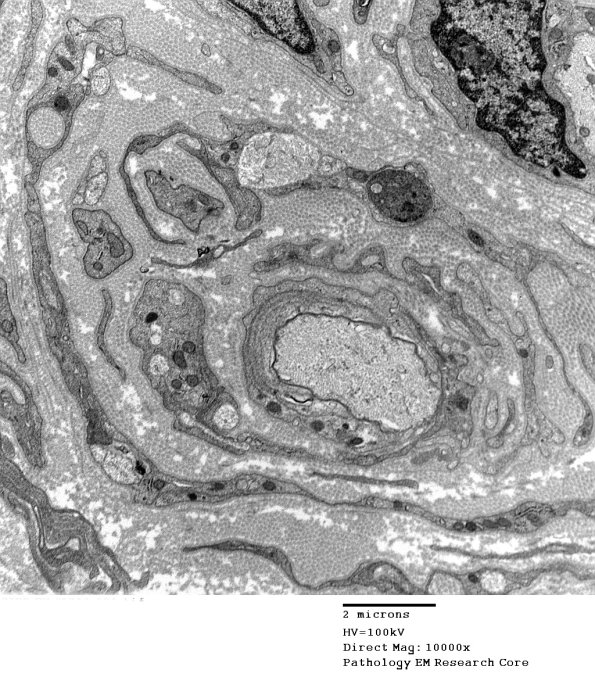

There are multiple well-formed onion bulbs surrounding thinly myelinated central axons. (electron micrographs)